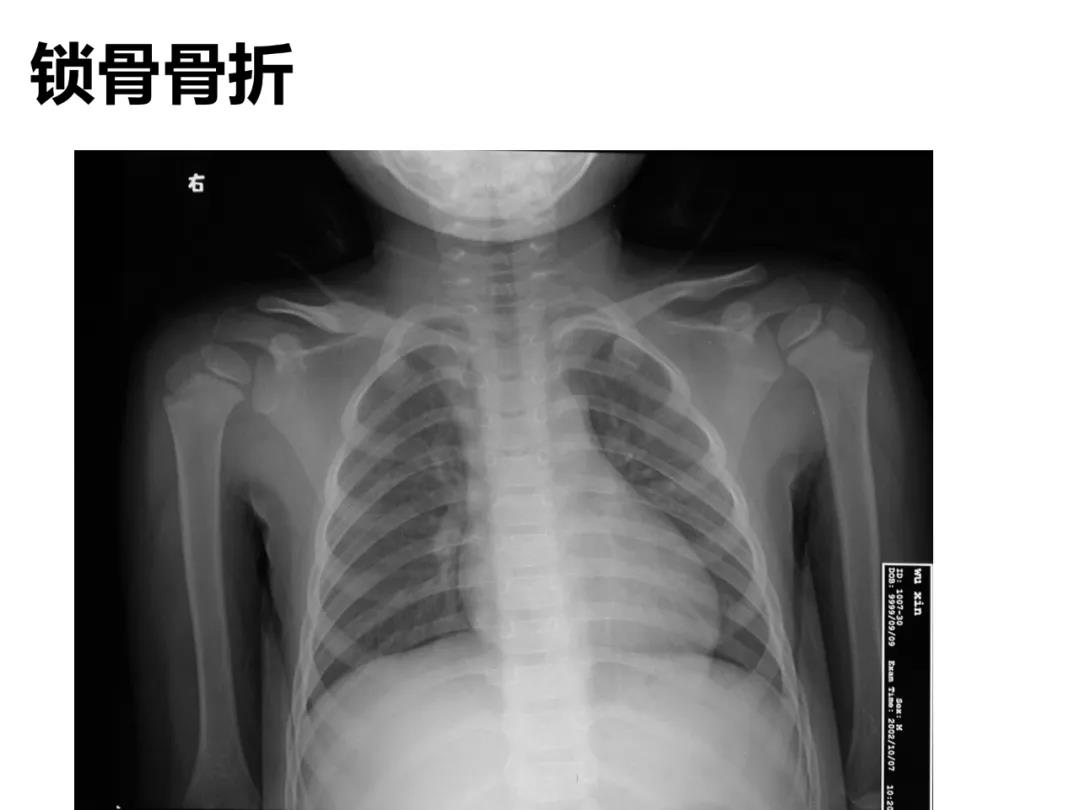

小儿骨科X线片汇总,临床读片宝典!